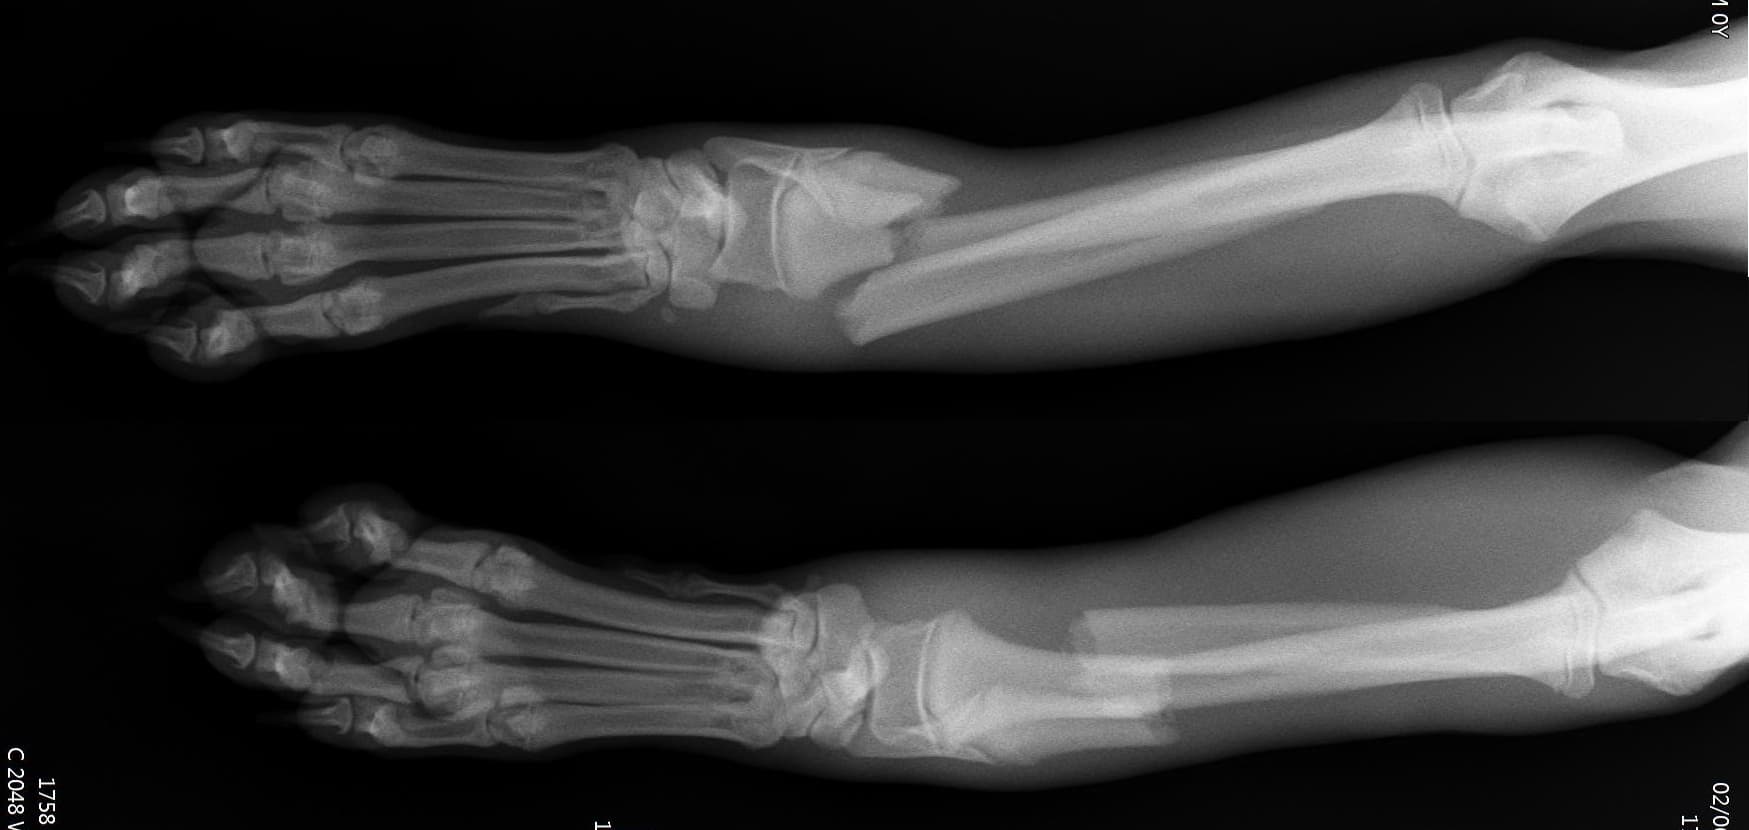

정형외과(Orthopedic Surgery)

정형외과 전공의 수의사가 직접 수술합니다.

호흡마취 시스템과 실시간 모니터링을 통해 안전한 마취가 가능합니다.

환자의 상태를 종합적으로 판단하여 수술을 진행합니다.

수술의 연장선상에 있는 재활 역시 최선을 다합니다.

0164 채널 CT 촬영을 통해서 신속하게 고화질 영상을 얻어, 종양 유래 확인 및 전이 평가, 간문맥단락증(PSS), 선천적 뼈 기형과 같은 심화된 진단을 할 수 있습니다.

11유명한 Stryker사 장비. 골절 수술, 절골등 다양한 정형/신경외과 수술시 사용

12정교한 정형외과 도구를 사용하여 신속 정확한 정형외과 수술이 가능

13수술 중 골절 상태 혹은 이식물 적용 후 상태 등 육안으로 명확히 확인하기 힘든 상태를 X-ray 확인하여 정확한 수술 결과를 만들어 내는 것이 가능